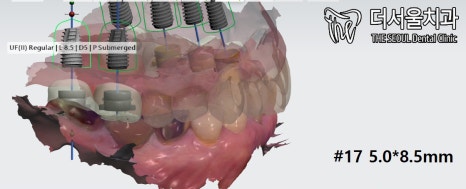

좀 더 정확한 데이터가 필요했기에

디지털 프로그램을 이용하여 체크했습니다.

2. 정밀 검사

먼저 20번대를 살펴보겠습니다.

이처럼 뼈가 좋지 않은 것을 알 수 있는데요.

골밀도가 좋지 않거나 폭이 좁거나 하죠?

25번은 뼈이식을 통해 뼈를 채워줘야 되었습니다.

염증까지 있는 것을 찾아볼 수 있었구요.

그래도 성남 치과의 기준으로 봤을 때,

큰 어려움은 없었습니다.

그럼 반대편을 살펴보겠습니다.

10번대 입니다.

20번대와 비교했을 때,

확실히 더 나은 것을 알 수 있습니다.

다만, 골밀도는 낮다는 점이 있네요 ^^;

다행히 임플란트 수술을 하는데 있어

크게 문제될 부분은 없었습니다.

성남 치과는 디지털 프로그램을 이용하여

분석 및 결과를 토대로 치료를 진행합니다.